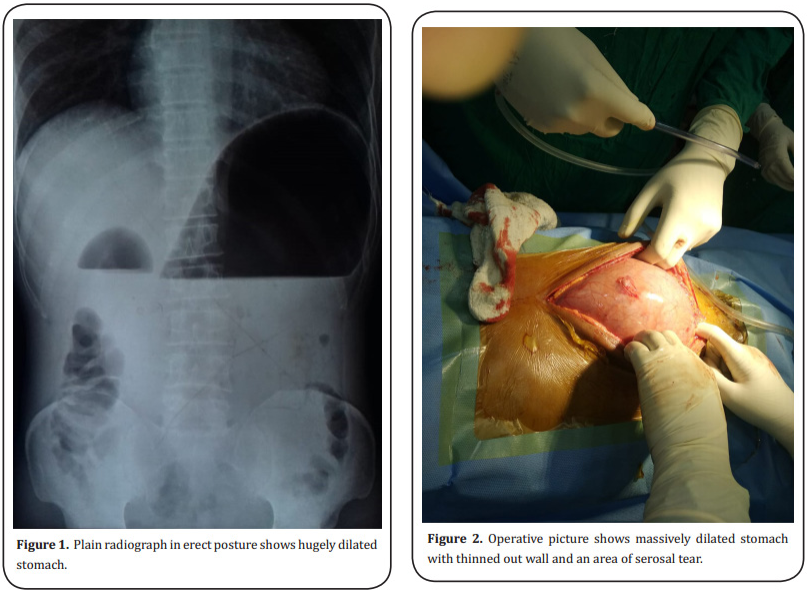

After admission the patient was resuscitated with normal saline and urgent upright abdominal x-ray was

done. The x-ray shows grossly dilated stomach (Figure

1) but there was no evidence of free gas under the diaphragm. A large bore nasogastric tube was inserted

At this stage conservative measures abandoned and the

patient was posted for emergency laparotomy after taking high risk consent. Standard midline vertical incision

given. As soon as the peritoneum opened, hugely distended stomach was seen extending from xiphisternum

to below umbilicus going towards the pelvis. The stomach wall was thinned out but there was no perforation

or obvious necrosis but a few patchy areas of slightly

dusky discolouration seen with one area of serosal tear (Figure 2). There was no rotation of the stomach and the

In our case, the stomach was hugely dilated and the greater curvature was below the umbilicus going towards the

pelvis. The gastric wall was thinned out and few patchy

areas of discolouration seen. No definite area of full

thickness gastric wall necrosis seen. There was one area

of serosal damage with impending perforation seen on